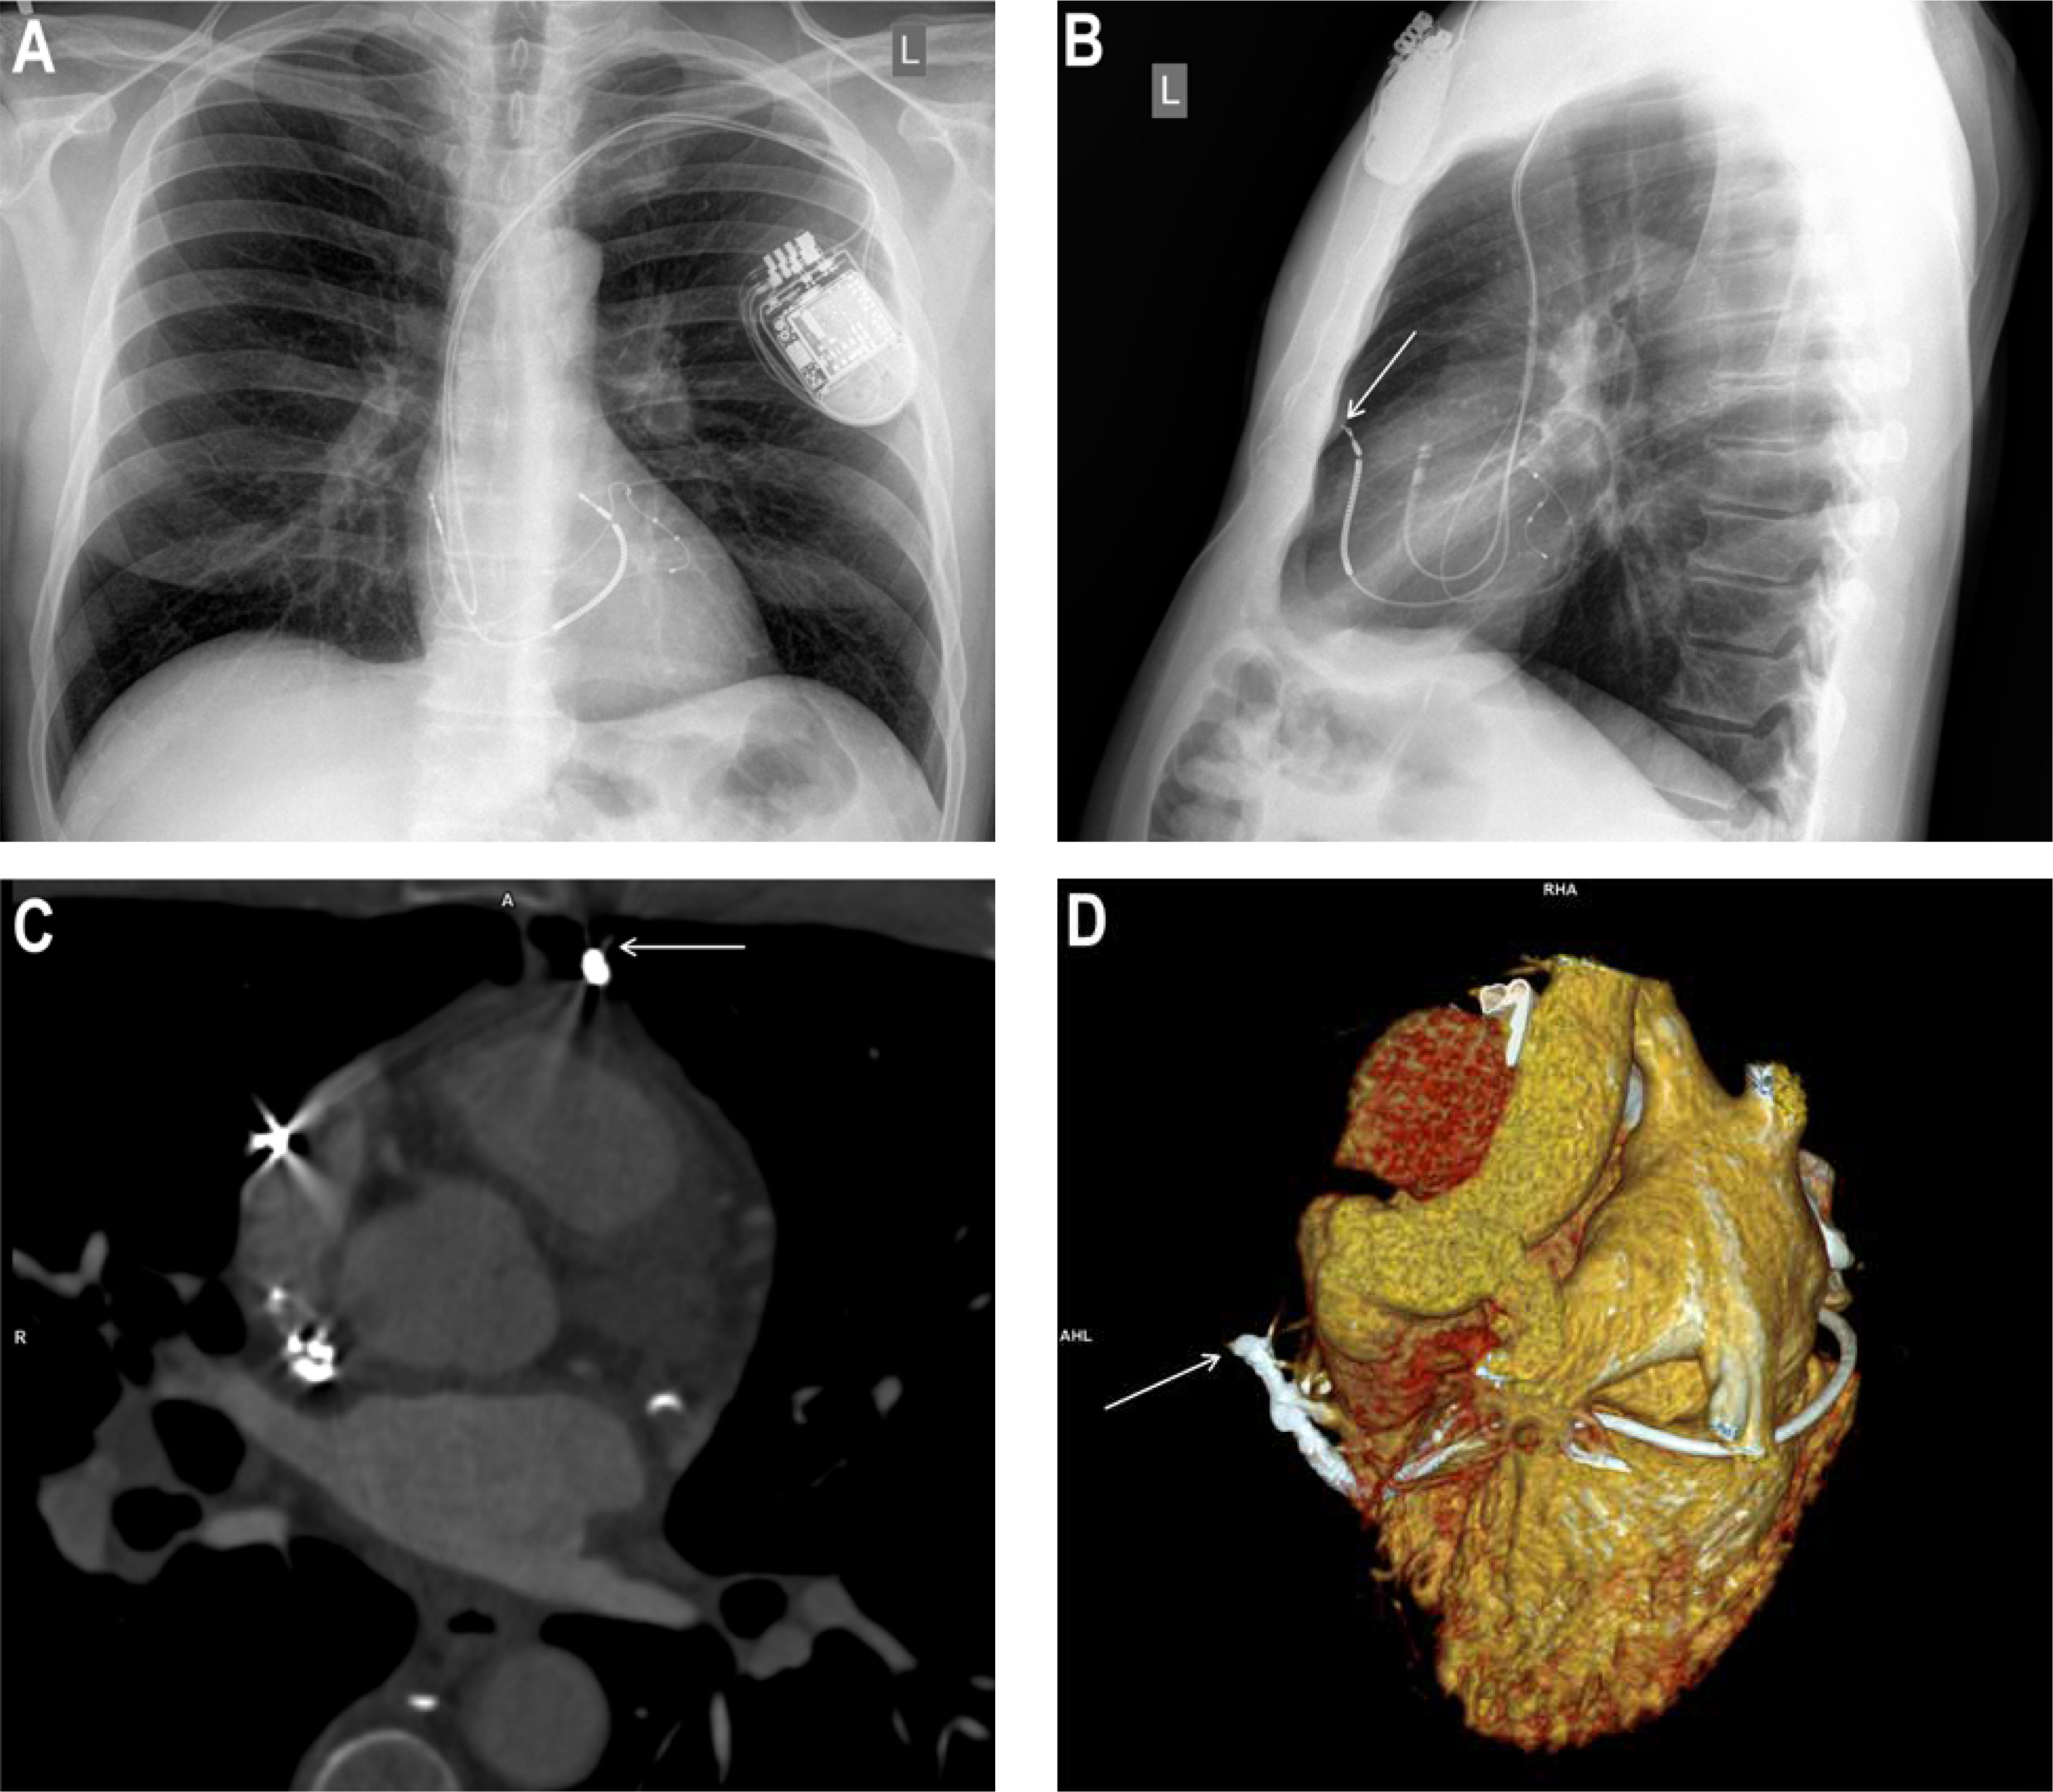

We present a case of a 59-year-old man referred to a tertiary cardiology centre for further investigation and treatment from a local hospital. He had a background of dilated cardiomyopathy. He underwent implantation of cardiac resynchronization therapy with a defibrillator (CRT-D) system in another hospital for secondary prevention of sudden cardiac death 18 months before (Figures 1 A, B). The patient reported an intermittent pricking sensation in the left side of the chest for the previous 12 months. The device interrogation showed unstable R-wave sensing values in the range 1.3–2.6 mV and gradually increasing stimulation thresholds on the right ventricular lead (RVL) for the previous 6 months. Impedance trends on all leads were within the normal range and stable. The patient had a single inappropriate shock due to lead noise, followed by right ventricular lead capture loss 2 weeks before the admission.

A, B – Chest X‑ray before the procedure. Lateral projection (B) view suggests a perforation of the heart by cardioverter-defibrillator lead Durata 7122Q65 located on the free wall of the right ventricle (arrow). C, D – Cardiac CT: MPR of right ventricle wall perforation (C) and VRT reconstructions of right ventricle lead perforation (D). Visible tip of the right ventricular lead adjacent to the border of the third bronchopulmonary segment and the lingula of the left lung, with no pericardial effusion or pneumothorax. Image of “dry” cardiac perforation through the cardioverter-defibrillator lead protruding beyond the myocardium by approximately 30 mm (C, D). Arrows indicate lead tip localized externally to the heart and pericardium

Chest X-ray was suspicious of cardiac perforation with a RVL (Figure 1 B). In transthoracic echocardiography, no increase in the pericardial fluid was observed. In cardiac computed tomography, the tip of the RVL was visible adjacent to the border of the third bronchopulmonary segment and the lingula of the left lung. There was no pericardial effusion or pneumothorax (Figures 1 C, D).

Lead perforations (LP) are rare (0.50%) but serious complications of cardiac implantable electronic device (CIED) implantation [1]. LP following CIED lead implantations are divided into acute (≤ 24 h), subacute (< 1 month), and delayed (> 1 month), according to their occurrence following implantation [2]. The rate of iatrogenic cardiac tamponade after CIED implantation is about 0.20% [3]. Delayed LP tends to present with lower rates of cardiac tamponade due to the self-sealing properties of the ventricular wall by muscle contraction, haemostasis, and subsequent fibrosis [4]. Risk factors for procedure-related iatrogenic cardiac perforation include apical or free wall placement of the RVL, over-torquing active fixation leads, and excessive lead slack as well as little experience of the operator [1]. The 2021 European Society of Cardiology pacing guidelines recommend placement of the lead in the mid-ventricular septum in patients at high risk of perforation, and the use of multiple fluoroscopic views to locate the lead in the right ventricle [5]. In this case, the most likely cause of the right ventricular free wall perforation was improper placement of an ICD lead on the free wall of the right ventricle combined with over-torquing its active fixation mechanism, which remained unrecognized during the implantation time (Figure 1 B).